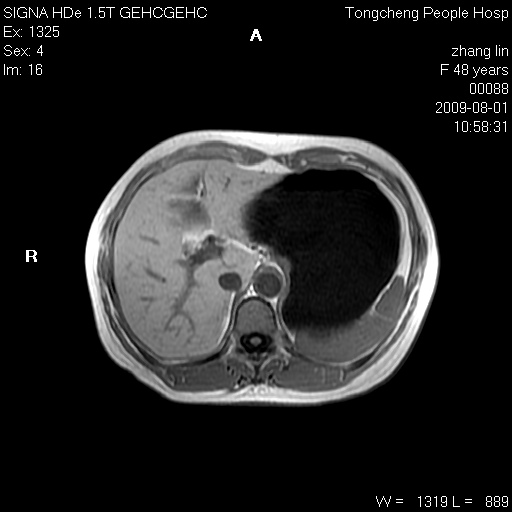

女,48岁。健康体检,彩超发现右肾占位性病变。平素健康。

临床诊断:右肾占位性病变,性质待定(囊肿?肿瘤?)。

上中腹部mr平扫+增强扫描,图像如下:

右肾上极见一类圆形病灶,t1wi呈等信号t2wi呈等高混杂信号,三期增强无强化,边界清---考虑囊肿出血。

同反相位均表现为等信号,病变无强化,考虑含蛋白的囊肿可能,弥散加权相或许有些帮助,

慢性胆囊炎